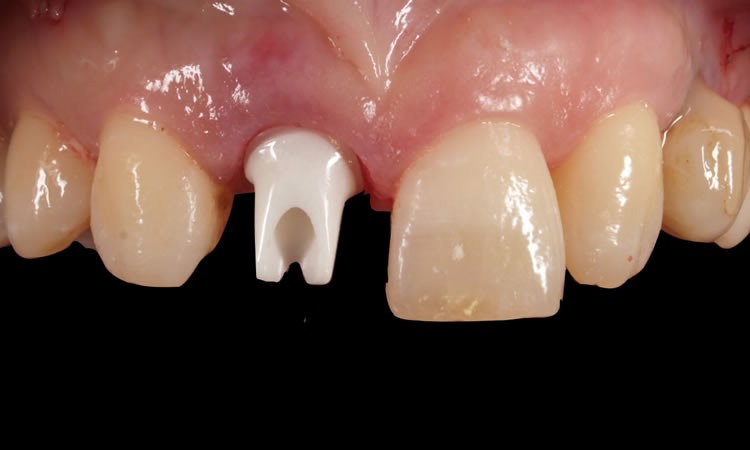

生体親和性が高いジルコニアアバットメント